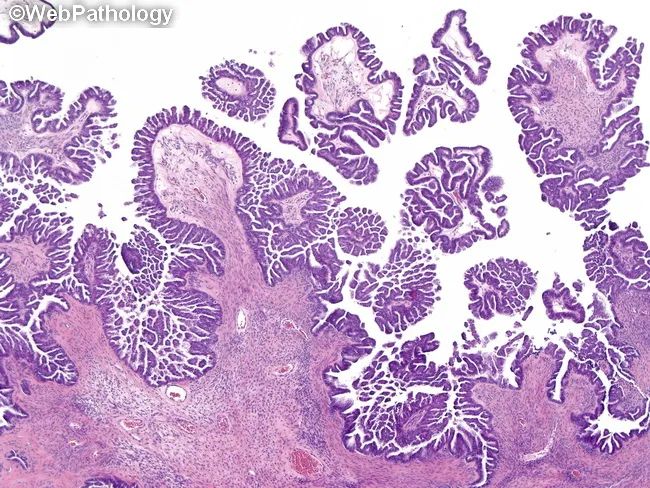

浆液性交界性肿瘤,微乳头亚型(micropapillary serous borderline tumor,MSBT) (又称低级别浆液性非浸润性癌)

(大体)多数双侧发生(约60%,高于经典型SBT),常累及卵巢表面(约50%),切面呈囊性或囊实性,囊内可见乳头

(形态)微乳头直接从大乳头直接发出(乳头直接分支,而非逐级分支)[特征] 微乳头轴心纤细,长:宽5:1 (细长的指状乳头)[特征]